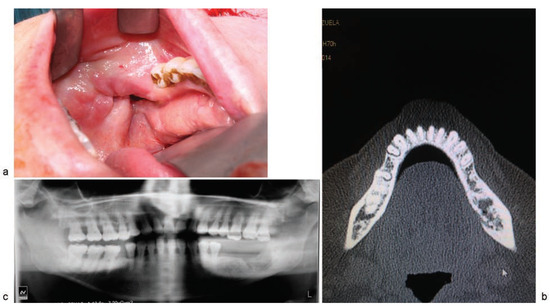

Despite a paradigm shift in anesthesia and trauma airway management, the craniomaxillofacial fracture (CMF) patients continue to pose a challenge. A prospective study was planned between April 2007 and March 2015 to investigate the safety, efficacy,...